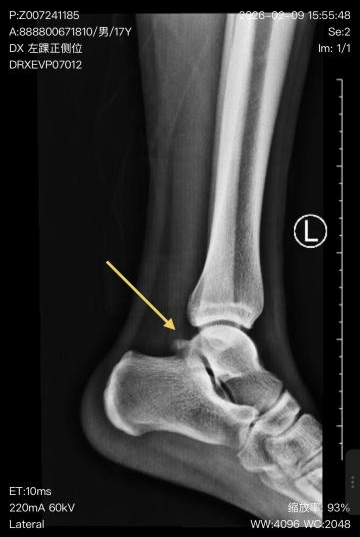

小王来到薛子超门诊就诊,经详细查体与影像学评估,“左踝距骨骨赘、后踝撞击综合征”诊断明确。后踝撞击综合征,是指踝关节后方骨性或软组织结构在踝跖屈(脚尖向下)时受到撞击、挤压,从而引起疼痛、肿胀和活动受限的一种常见运动损伤。该病好发于需要反复进行脚尖下压动作的人群,足球运动员正是高发群体之一——无论是射门、传球还是盘带,都需要频繁的踝跖屈动作。此外,芭蕾舞演员、体操运动员以及长期穿高跟鞋的人群也易患此病。若不及时治疗,可能导致软骨损伤、骨赘形成,甚至发展为创伤性关节炎,严重影响运动生涯和生活质量。